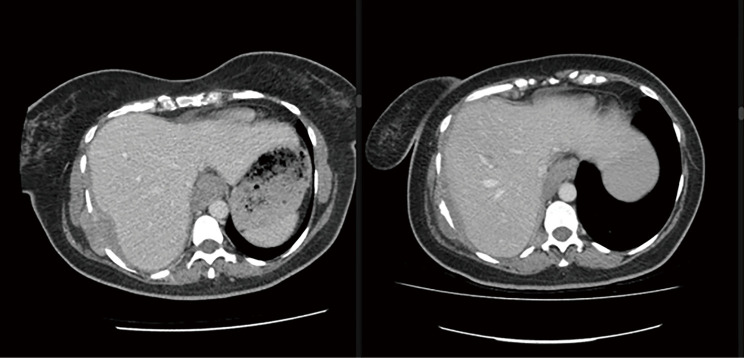

Case description: We present a case of a 42-year-old woman, with no asbestos exposure history, diagnosed with metastatic PM. Initial treatment with immunotherapy showed limited efficacy. Given the rarity in young females, she opted for genetic testing via "The Screen Project", revealing a pathogenic ATM mutation. Due to enhanced radiosensitivity in ATM mutation carriers, to reduce adverse events conventional palliative radiotherapy (RT) was chosen over stereotactic hypofractionated RT. A follow-up computed tomography (CT) scan after 4 weeks indicated disease burden reduction.